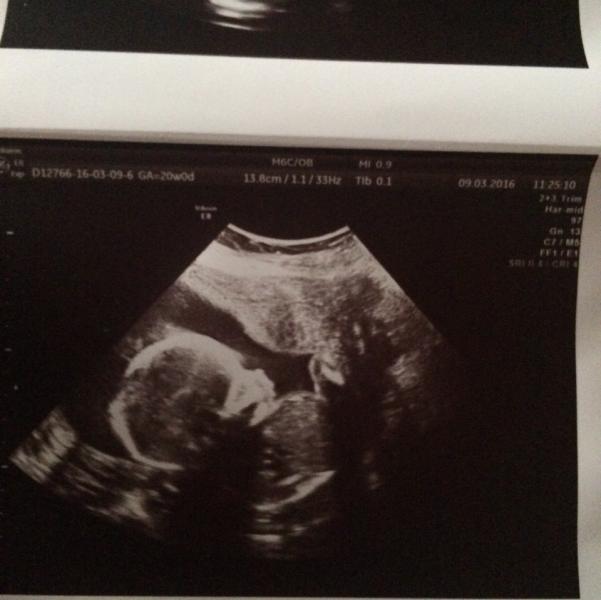

Добренького вечера) сегодня у Нас счастливый день мы с мужем узнали что у нас будет Девочка)) все эти 20 недель почему то у меня было предположение что будет мальчик, и у мужа родителей это будет 6я внученька. Что хочу сказать обследовались мы в Маме Вите у Полтнева , очень хороший врач узист хоть и очень молодой) рассказал что наша крошка развивается очень хорошо все ручки ножки, пальчики , глазки, носик ротик все на месте) этому мы были очень рады, со 100% он сказал что девочка, хотя личико и...